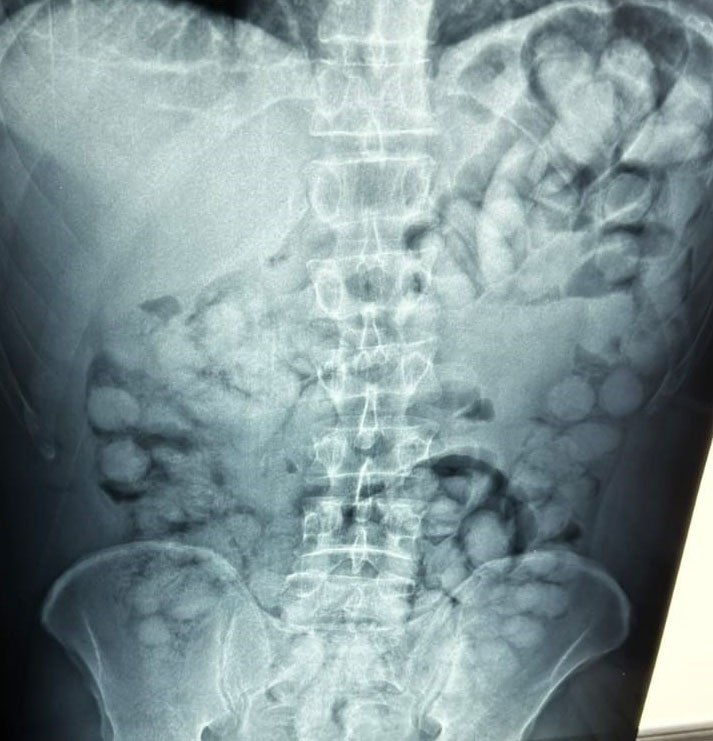

All in all, the cocaine carried by the alleged “drug mule” exceeded one kilo, one of the largest such hauls ever recorded in the country with a smuggling method deemed as highly dangerous for the carrier.

Police released x-rays showing the man’s abdomen filled with the plastic containers filled with the drugs.